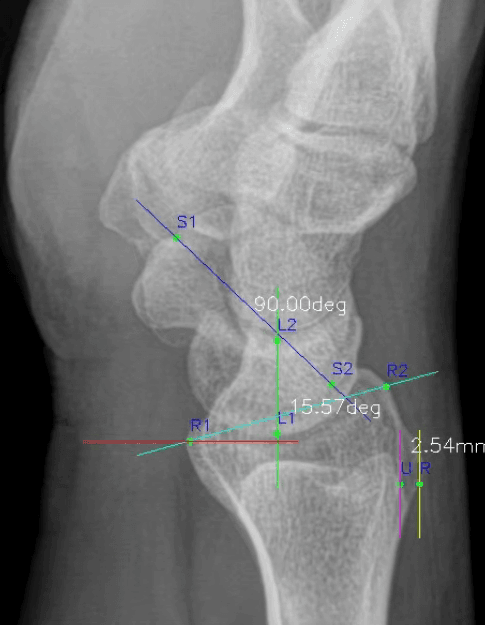

WALK101, Wrist_Lat_AIX 출시… 손목 X-ray(LAT) 자동 측정으로 임상 파이프라인 확장

Wrist_Lat_AIX는 손목 Lateral X-ray에서 주요 불안정 진단 관련 지표를 자동 측정하는 AI 솔루션으로, SaMD 1등급 의료기기 인증을 획득했습니다.